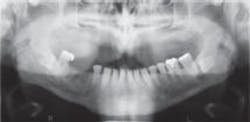

About a year ago, something happened that changed my mind. I had referred a new patient to an oral surgeon, requesting an evaluation for the removal of impacted mandibular third molars. When the oral surgeon took an extraoral panoramic film, he discovered a significant radiolucent lesion, a 2.5 cm odontogenic keratocyst involving the ramus. It had been there for a long time, but the intraoral radiographic exams that had been performed in the past had missed it.

Recently, I performed an exam on a new patient and discovered a large cyst. It obviously had been there for a long time, but could not be clearly visualized with routine intraoral X-rays. Removing this lesion will require extensive surgery. Had it been detected sooner, treatment would be far less traumatic to the patient.

In this case, the cyst looked benign. The pathology report will determine the actual diagnosis. The possibility exists, of course, that a future patient could present with a malignant lesion. Detecting an aggressive tumor early could save a patient's life. Detecting calcifications of the carotid artery could also help a patient avert an impending stroke.